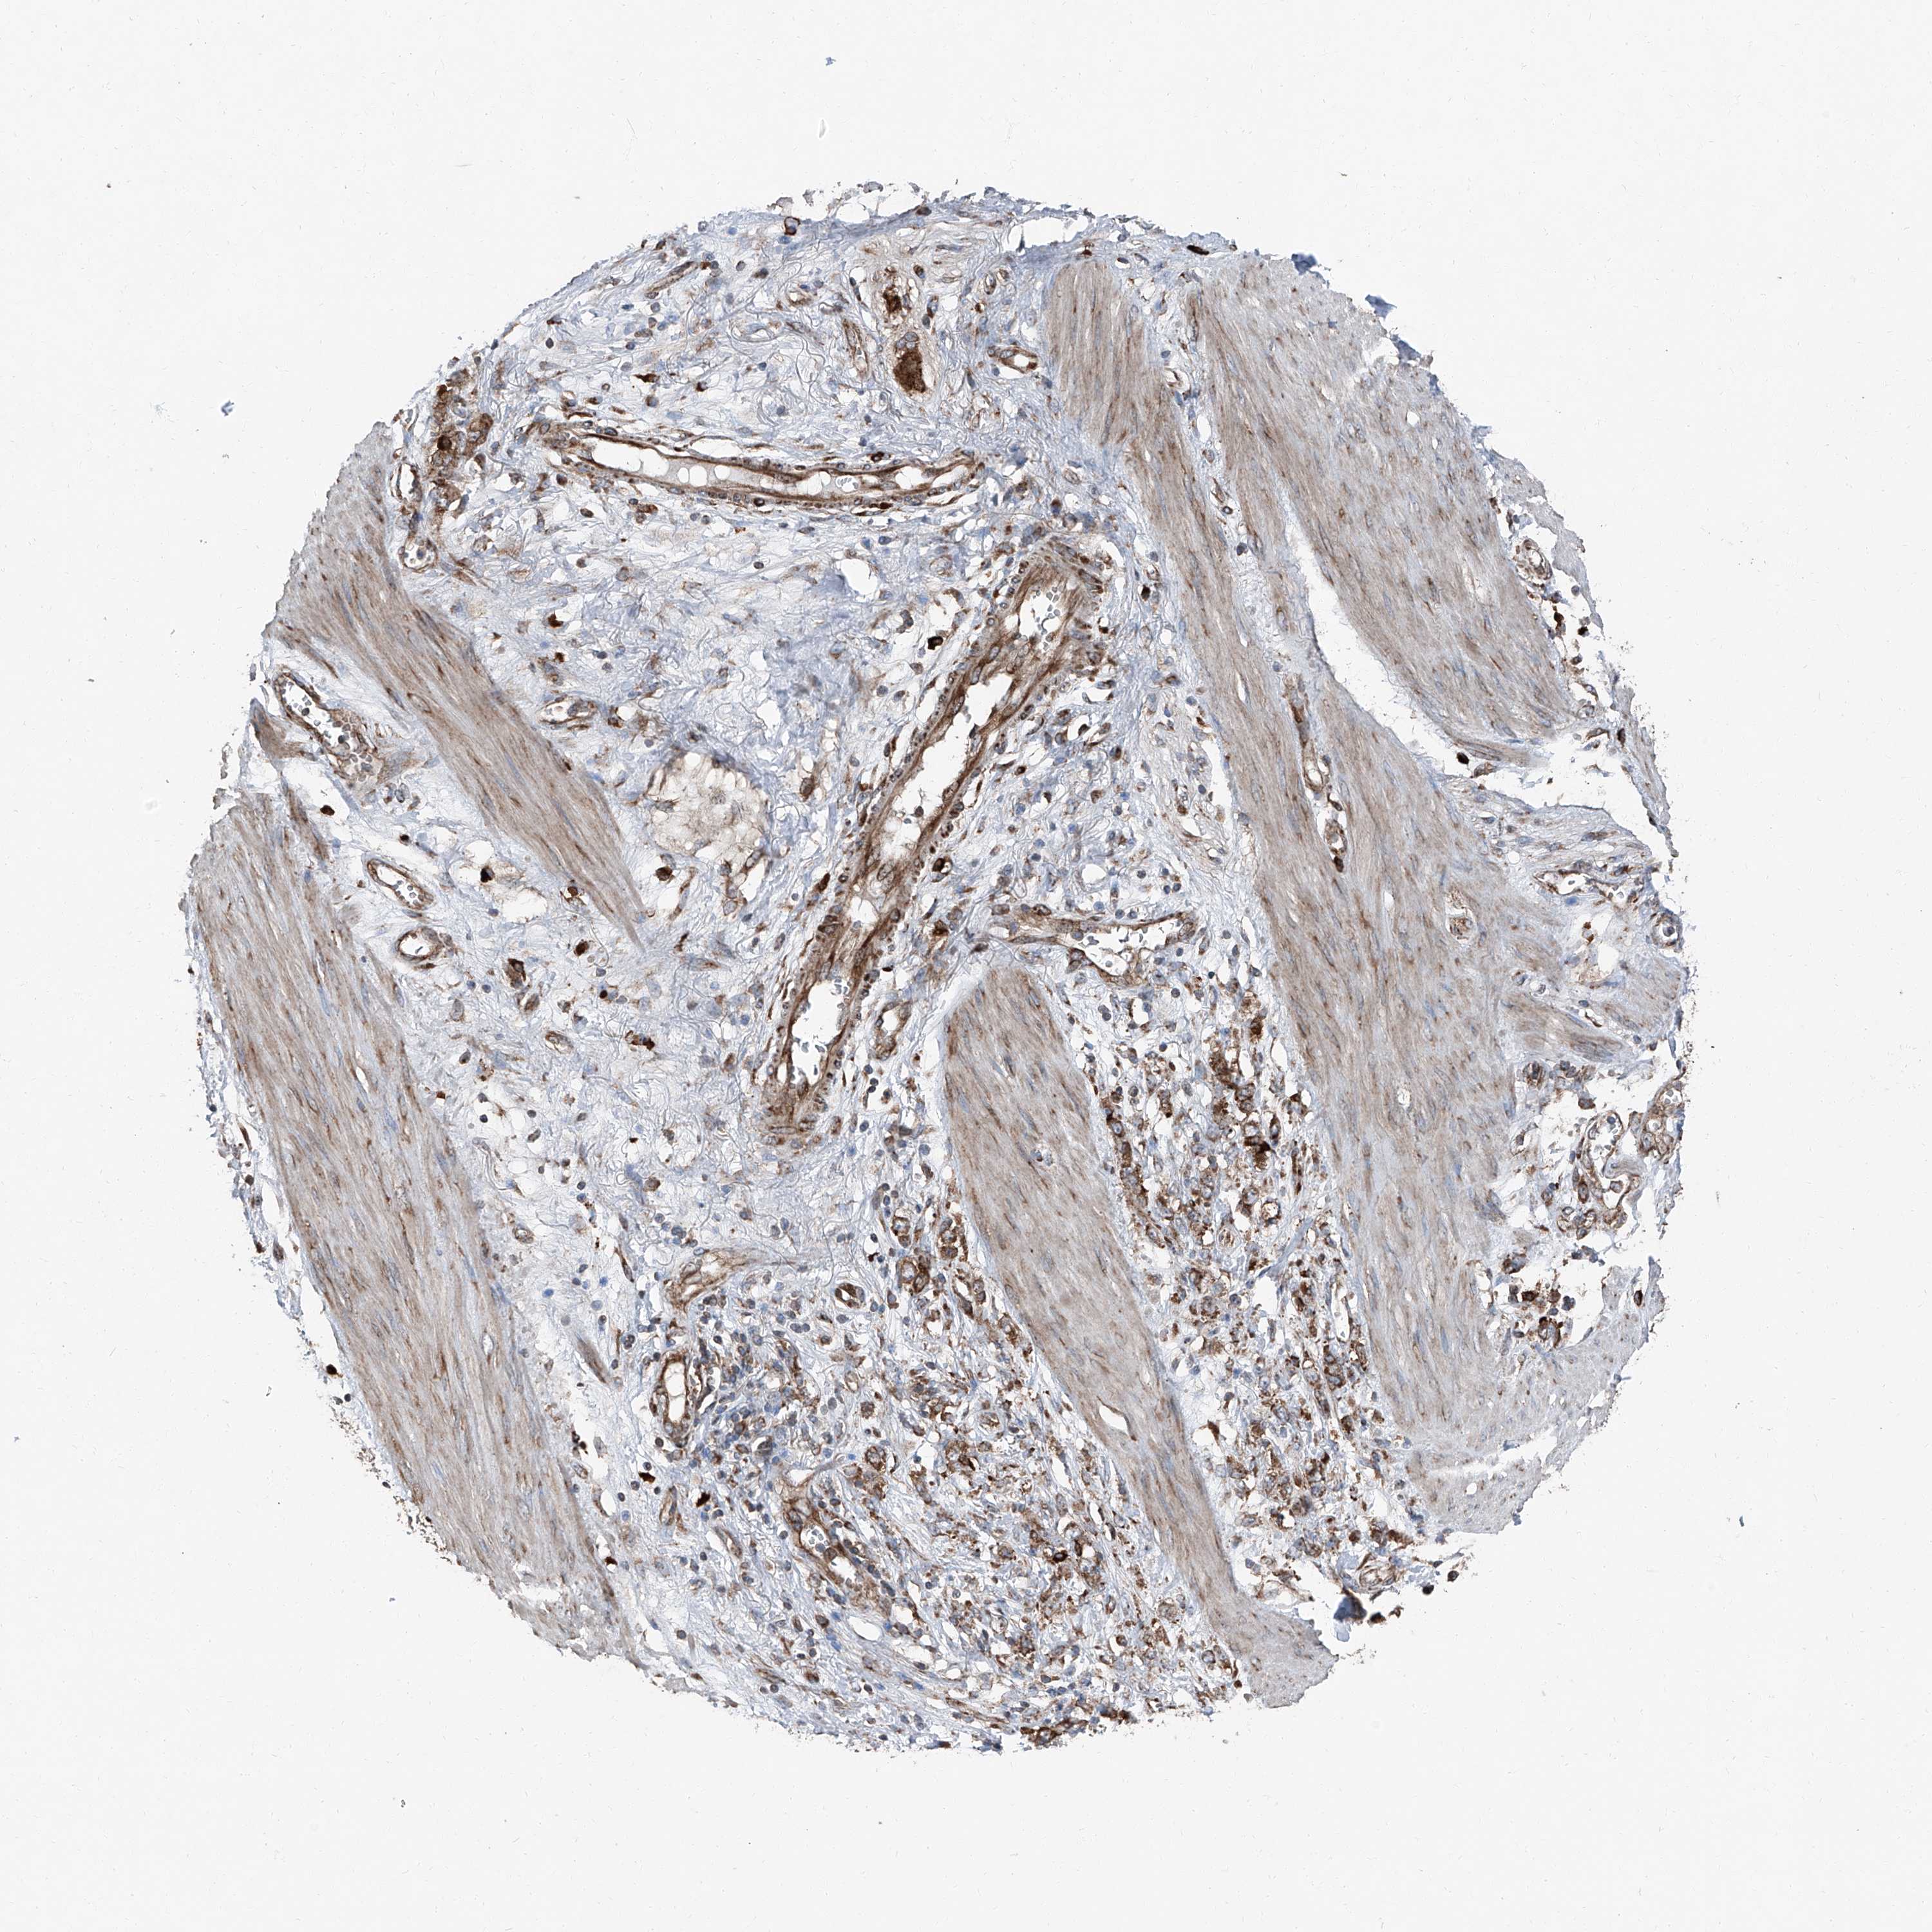

STOMACH CANCER - Protein expressioni

A mouse-over function shows sample information and annotation data. Click on an image to view it in a full screen mode. Samples can be filtered based on level of antibody staining by selecting one or several of the following categories: high, medium, low and not detected. The assay and annotation is described here.

Antibody stainingi

Antibody staining in the annotated cell types in the current human tissue is reported as not detected, low, medium, or high, based on conventional immunohistochemistry profiling in selected tissues. This score is based on the combination of the staining intensity and fraction of stained cells.

Each image is clickable and will lead to virtual microscopy that enables deeper exploration of all samples and also displays staining intensity scores, fraction scores and subcellular localization as well as patient and tissue information for each sample.

Antibody HPA028516

Antibody HPA073571

Staining

High

Medium

Low

Not detected

Intensity

Strong

Moderate

Weak

Negative

Quantity

>75%

75%-25%

<25%

None

Location

Nuclear

Cytoplasmic/membranous

Cytoplasmic/membranous,nuclear

Adenocarcinoma, NOS

Adenocarcinoma, High grade